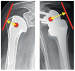

Die Gelenke im menschlichen Körper werden durch Bänder und Muskeln stabilisiert. Die Muskulatur hat meistens größere Hebelarme zur Erzeugung von Drehmomenten als die Bänder, daher ist es wichtig, im Rahmen der Rehabilitation die Muskulatur zu aktivieren. Die Gelenkskräfte werden dadurch verringert. Prothesen wie z. B. die inverse Schulterprothese erzeugen vergrößerte Hebelarme und ermöglichen bei gleicher Muskelkraft größere Drehmomente. Um gute Rehabilitation zu gewährleisten, ist es wichtig, Kräfte und Drehmomente in den Gelenken zu verstehen. Dazu ist es notwendig, die Drehzentren und die Hebelarme der wirksamen Kräfte zu bestimmen.